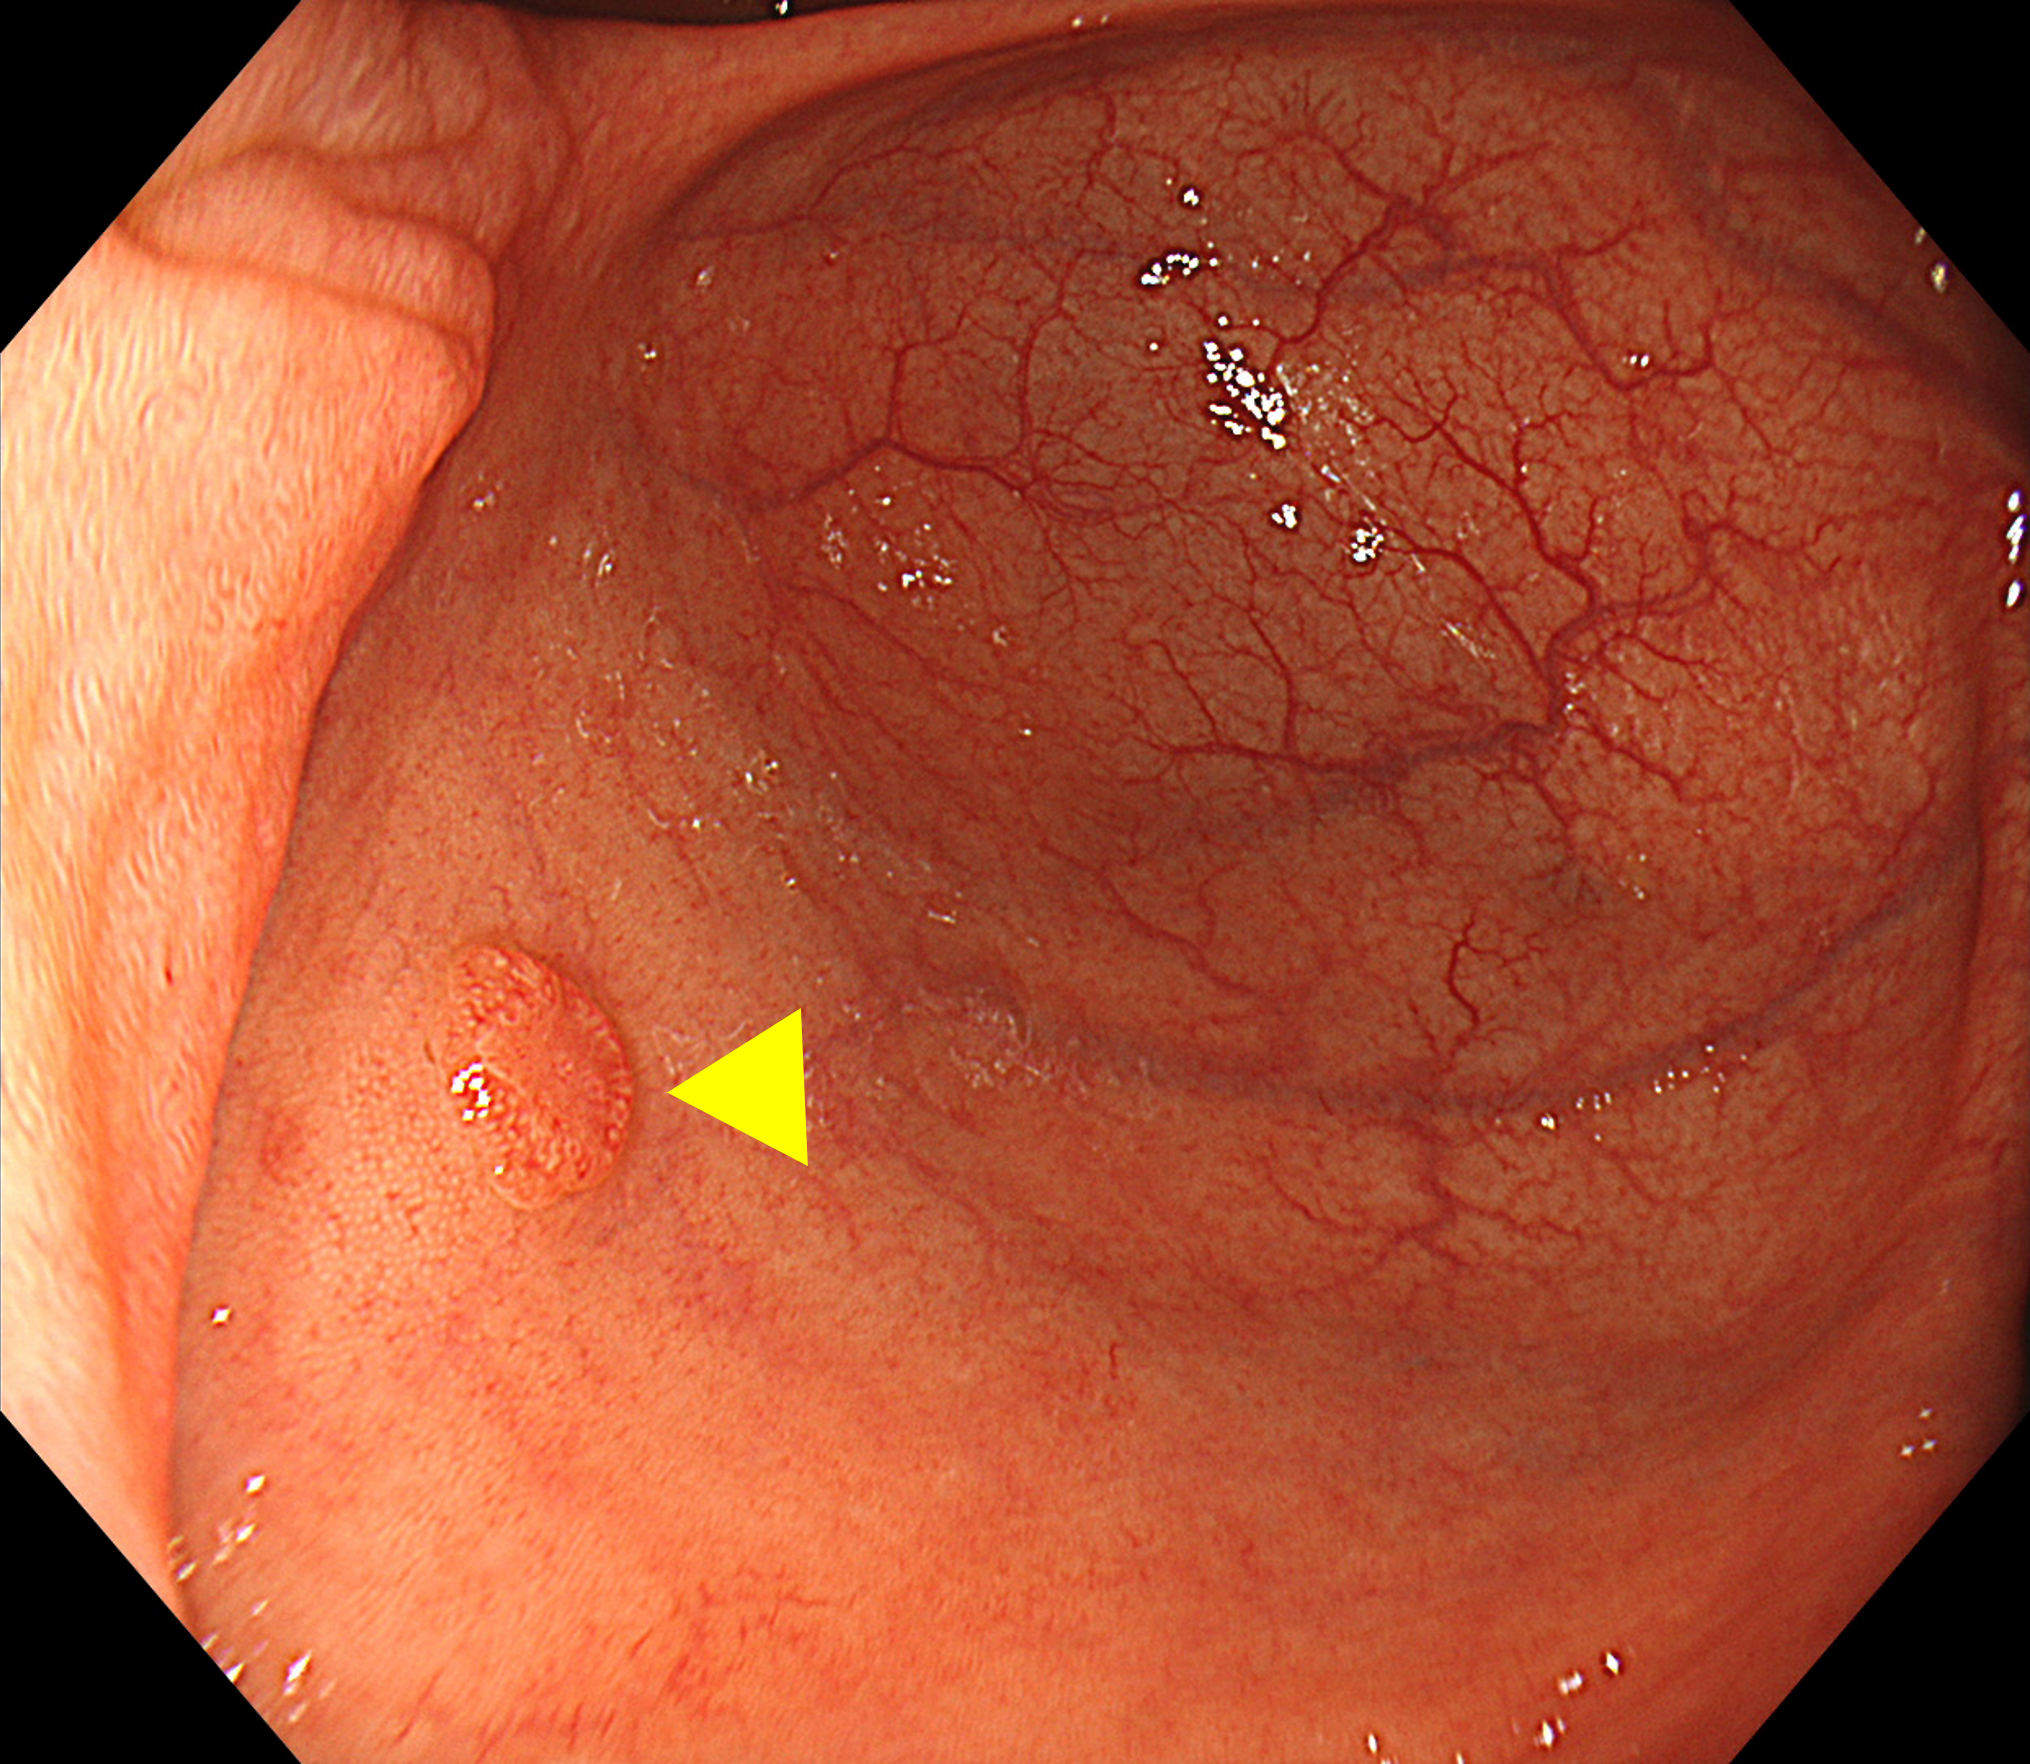

• ※Figure 3. 脾彎曲部の観察

(a) 抜去してくるのみだと屈曲部のひだ裏が観察しづらい

•

(b)Pushすると管腔が開き、ひだ裏が観察しやすくなる